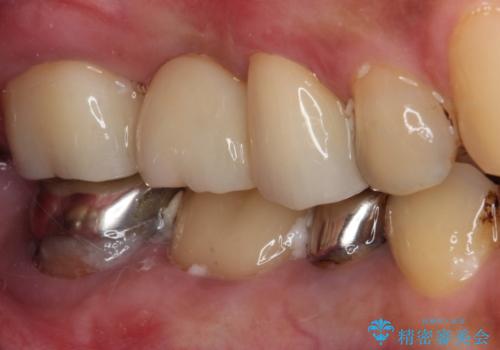

虫歯が大きく進行していましたが、歯髄(神経組織)にまで及ぶものではなかったため、無事に虫歯治療を行うことができました。

歯石もしっかりと除去したことで、周辺の腫れていた歯肉も引き締まり、健全な状態となりました。